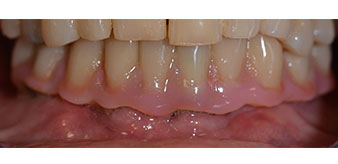

La paciente de 64 años se presentó con una dentición residual compuesta por las piezas dentales 38, 33 y 43 en el maxilar inferior y con una prótesis temporal fijada con ganchos en el maxilar inferior (figs. 1 y 2).